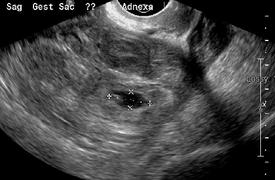

An ultrasound showing a gestational sac with fetal heart in the fallopian tube has a very high specificity of ectopic pregnancy. Transvaginal ultrasonography has a sensitivity of at least 90% for ectopic pregnancy.[4] The diagnostic ultrasonographic finding in ectopic pregnancy is an adnexal mass that moves separately from the ovary. In around 60% of cases, it is an inhomogeneous or a noncystic adnexal mass sometimes known as the "blob sign". It is generally spherical, but a more tubular appearance may be seen in case of hematosalpinx. This sign has been estimated to have a sensitivity of 84% and specificity of 99% in diagnosing ectopic pregnancy.[4] In the study estimating these values, the blob sign had a positive predictive value of 96% and a negative predictive value of 95%.[4] The visualization of an empty extrauterine gestational sac is sometimes known as the "bagel sign", and is present in around 20% of cases.[4] In another 20% of cases, there is visualization of a gestational sac containing a yolk sac or an embryo.[4] Ectopic pregnancies where there is visualization of cardiac activity are sometimes termed "viable ectopic".[4]

A "blob sign", which consists of the ectopic pregnancy. The ovary is distinguished from it by having follicles, whereof one is visible in the field. This patient had an intrauterine device (IUD) with progestogen, whose cross-section is visible in the field, leaving an ultrasound shadow distally to it.